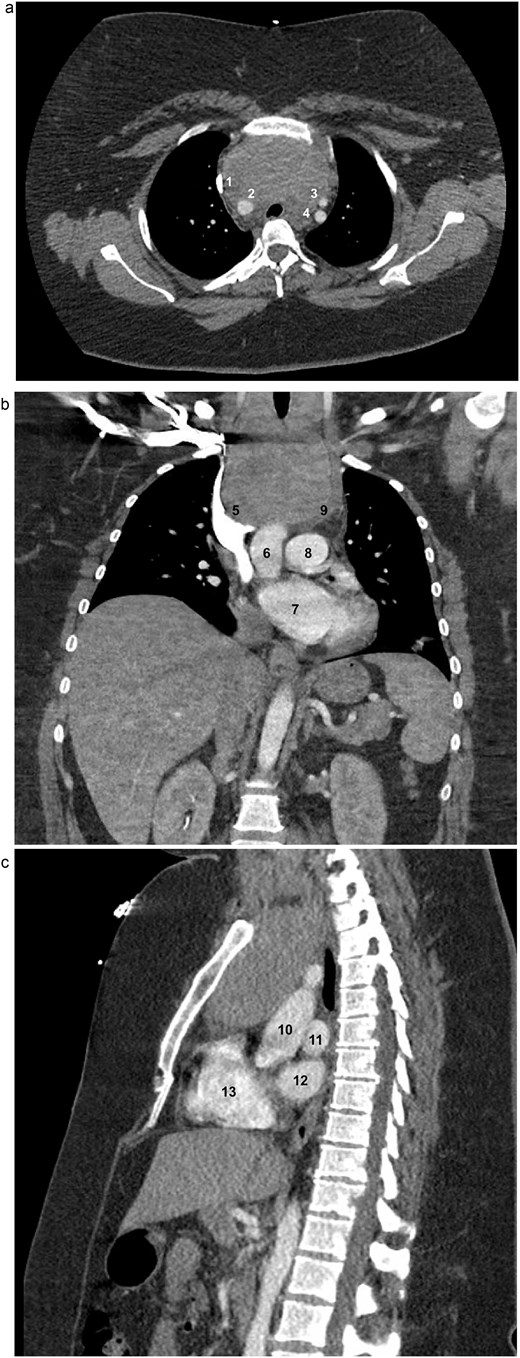

A 33-year-old woman with a history of morbid obesity (BMI = 47 kg/m2), gestational hypertension, and preeclampsia was incidentally found to have a large cervical mass identified during workup for fevers. Computed tomography (CT) scan revealed a 9.1 × 5.7 × 10.4 cm thyroid mass with extensive substernal extension and tracheal compression (Fig. 1a–c). Her family history was notable for thyroid cancer in her father and two paternal aunts. Due to the size of the mass, associated compressive symptoms, and strong family history of malignancy, a total thyroidectomy was recommended using a combined cervical and trans-sternal approach. Fine-needle aspiration demonstrated benign findings consistent with follicular colloid tissue. Given her body habitus and elevated risk of wound complications and sternal dehiscence, the sternal extension was limited to a partial upper sternotomy.

Axial (a), coronal (b), and sagittal (c) contrast-enhanced CT images of the chest demonstrating marked thyromegaly with retrosternal and intrathoracic extension (craniocaudal dimension up to 14 cm), resulting in tracheal narrowing at the thoracic inlet. In the axial view, the (1) superior vena cava (SVC), (2) brachiocephalic artery, (3) left common carotid artery, and (4) left subclavian artery are identified. In the coronal view, the (5) SVC, (6) ascending aorta, (7) left atrium (LA), (8) main pulmonary artery, and (9) brachiocephalic vein are identified. In the sagittal view, the (10) aorta, (11) left pulmonary artery, (12) LA, and (13) right ventricle are identified.